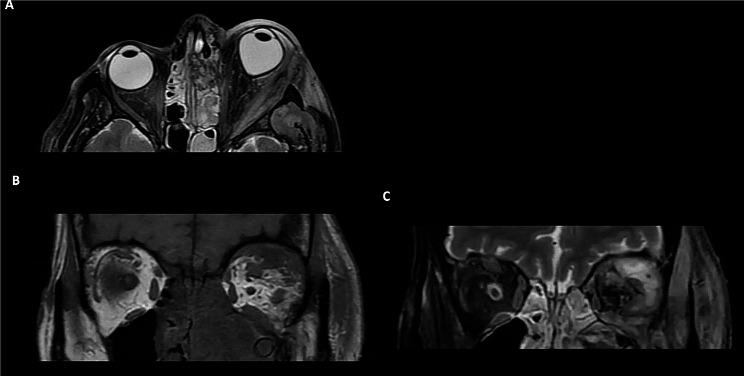

Four patients with odontogenic orbital cellulitis were identified for inclusion. There was an equal proportion of men and women with a mean age of 43 years (range 25-56 years). All patients presented with an orbital compartment syndrome, with visual acuity of counting fingers (n = 1, 25%), hand movements (n = 1, 25%) and no perception of light (n = 2, 50%). The organisms implicated were Streptococcus milleri (n = 3, 75%) and Streptococcus constellatus (n = 1, 25%). MRI findings showed a subperiosteal abscess was present in all cases, which was characterised radiologically as a T1-hyperintense, T2 minimally hyperintense collection with restricted diffusion and a low apparent diffusion coefficient signal. Final visual acuity ranged from 6/6 to no light perception. One patient required an orbital exenteration due to extensive necrosis with sepsis and systemic deterioration.

确定纳入4例牙源性眶蜂窝织炎患者。男女比例相等,平均年龄43岁(范围25 - 56岁)。所有患者均出现眶间隔综合征,视力分别为指数(n = 1,25%)、手动(n = 1,25%)和无光感(n = 2,50%)。涉及的微生物为米勒链球菌(n = 3,75%)和星座链球菌(n = 1,25%)。MRI表现显示所有病例均存在骨膜下脓肿,其影像学特征为T1高信号、T2轻度高信号,弥散受限,表观扩散系数信号低。最终视力范围从6/6到无光感。1例患者因广泛坏死伴脓毒症和全身状况恶化而需要进行眶内容摘除术。